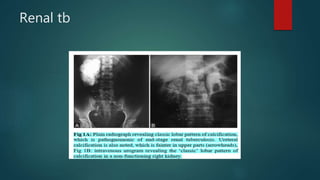

Renal tb

Papillary necrosis